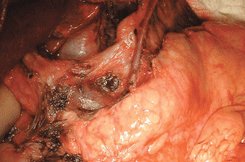

| Стандартная радикальная гастрэктомия (СРГ) D2 ;(см. рис. 6–14 на цветной вклейке) | + | + | — |

Рисунок 6. Выделена правая желудочная артерия (на лигатуре)

Рисунок 7. Лимфодиссекция зоны чревного ствола (выделены левая желудочная вена и левая желудочная артерия на протяжении)

Рисунок 8.Бурсосегментэктомия

Рисунок 9. Лимфодиссекция печеночно-двенадцатиперстной связки (видны воротная вена и общая печеночная артерия)

Рисунок 10. Окончательный вид послеоперационной раны после лимфодиссекции D2

Рисунок 11. Мобилизация панкреато-лиенального комплекса с лимфодиссекцией ворот селезенки

Рисунок 12. Окончательный вид панкреатолиенального комплекса после лимфодиссекции по ходу селезеночных артерии и вены в воротах селезенки

Рисунок 13. Трансхиатальная мобилизация пищевода с лимфодиссекцией заднего средостения

Рисунок 14. Окончательный вид раны после трансхиатальной резекции пищевода и формирования медиастинального пищеводно-кишечного анастомоза